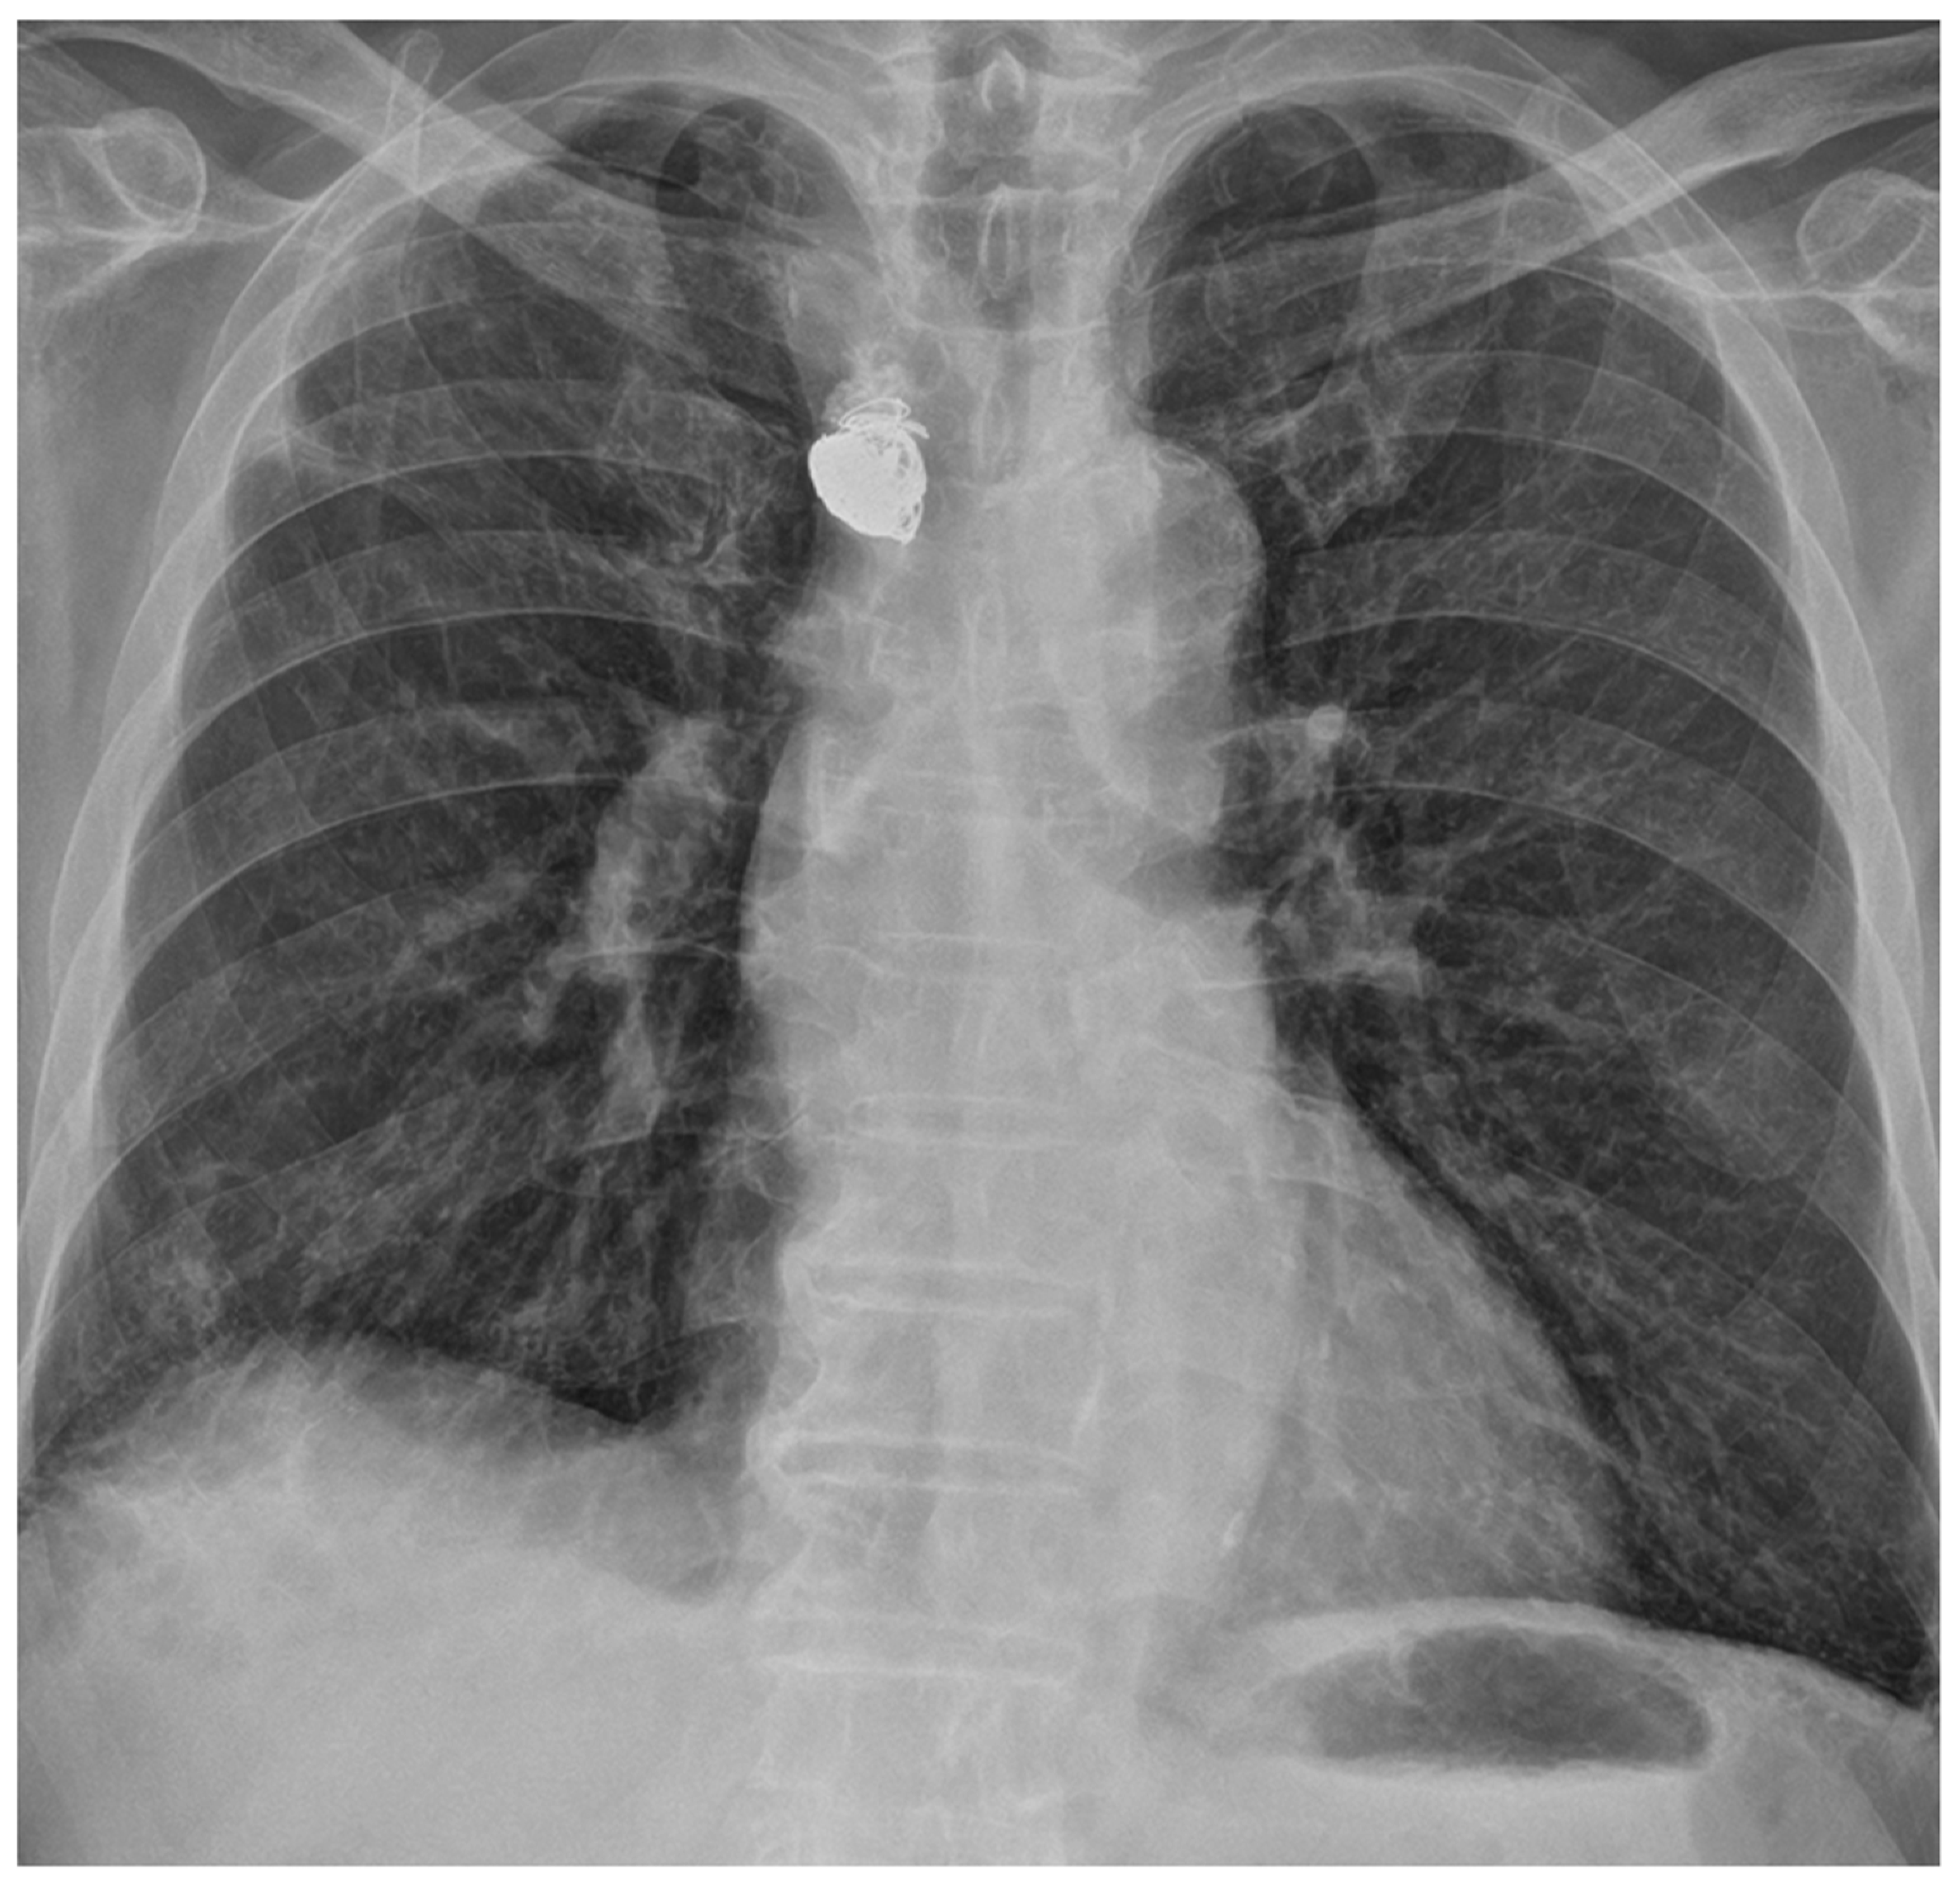

2. Case Presentation